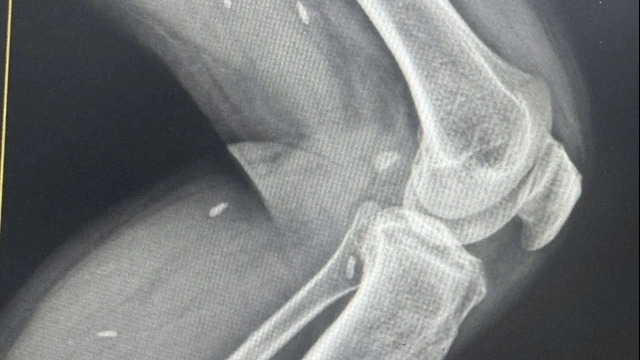

Nam bệnh nhân L.V.S (75 tuổi, trú tại Móng Cái) nhập viện trong tình trạng nói khó, liệt nửa người trái. Qua thăm khám và chụp cắt lớp vi tính sọ não, các bác sĩ phát hiện khối tụ máu dưới màng cứng bán cầu phải số lượng lớn do chấn thương sọ não.

| Ca mổ não diễn ra khi bệnh nhân vẫn tỉnh và có ý thức, cho phép các bác sĩ theo dõi trực tiếp phản xạ thần kinh trong suốt quá trình phẫu thuật |